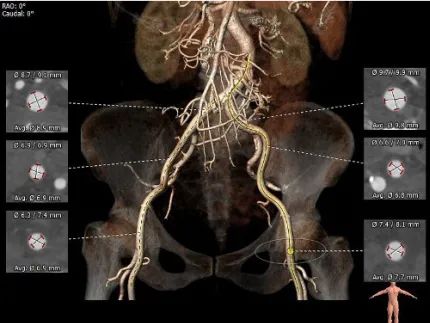

双侧股动脉管径尚可,主动脉弓部夹角锐利(54°)、弓部宽度较短(最短处仅58.8mm),降主动脉轻度扭曲,输送器过弓、跨瓣难度较高。